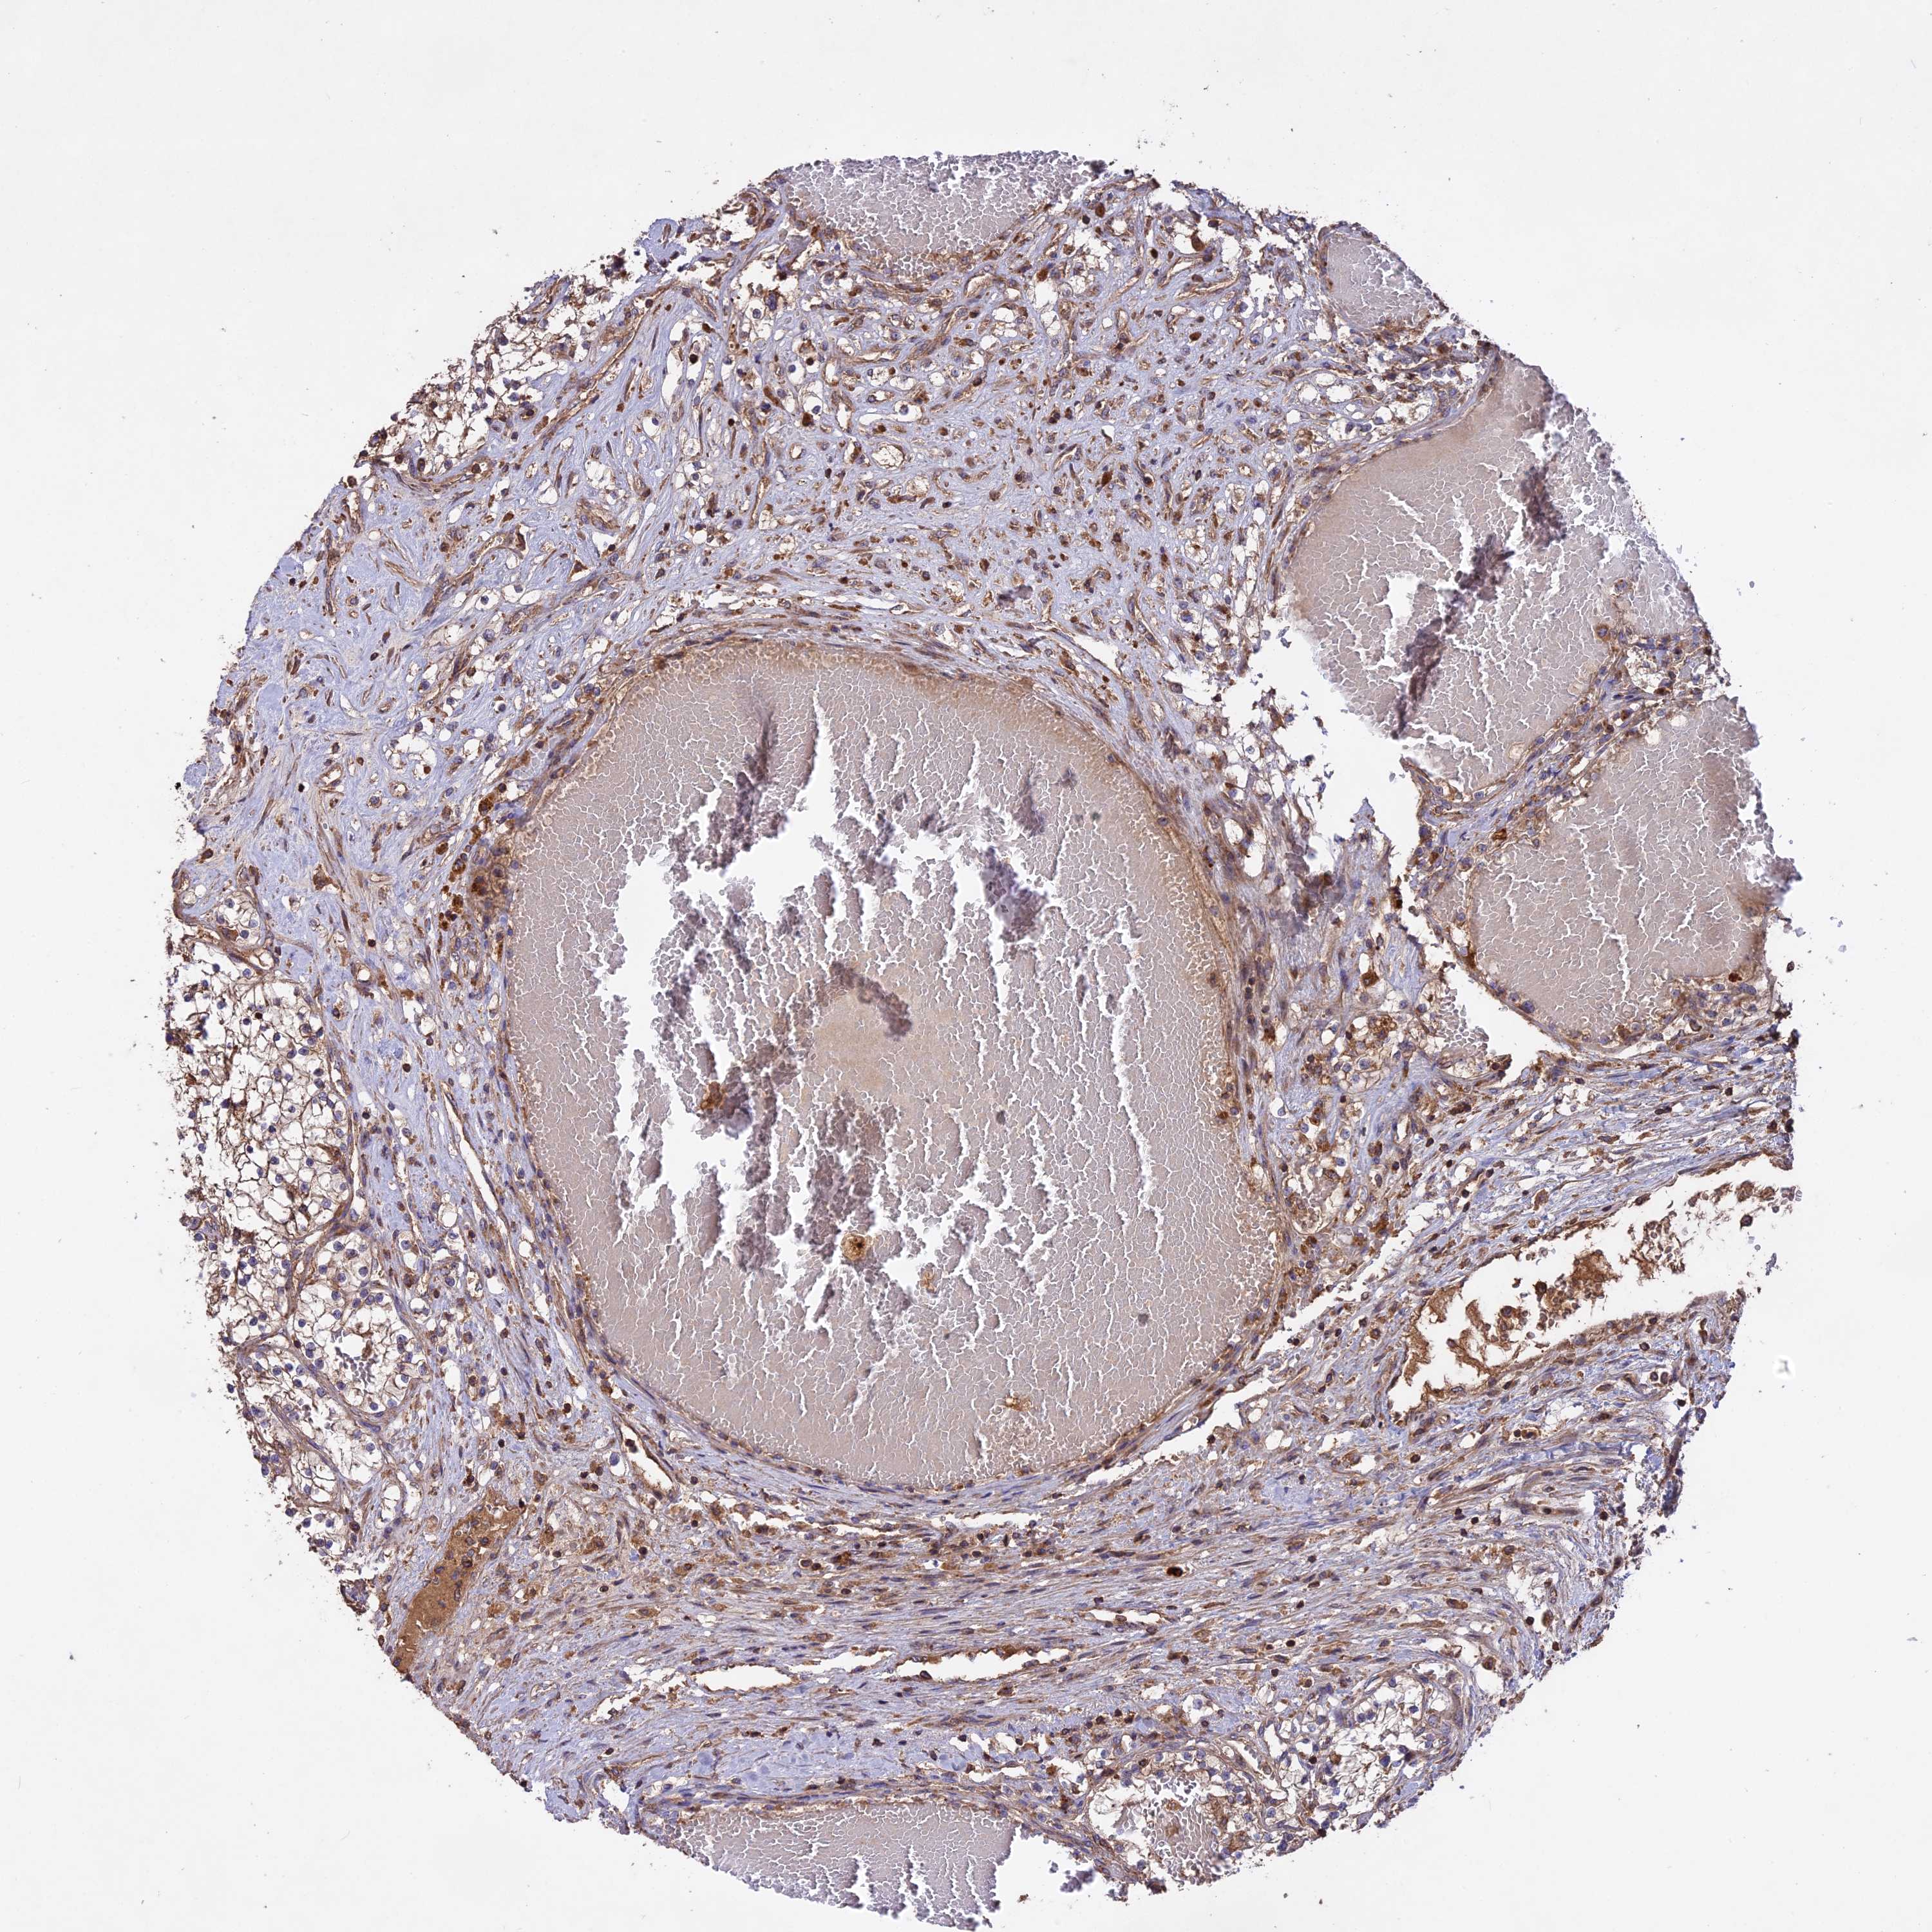

CANCER RENAL CANCER Show tissue menu

KICH TCGA KIRC TCGA KIRC VALIDATION KIRP TCGA PROTEIN RCC CPTAC PROTEIN EXPRESSION